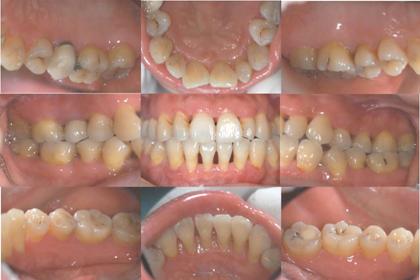

治疗前口内相

患者,女,43岁。近5年来,刷牙及咬硬物出血频繁,量中可自行停止。自述偶有牙龈肿痛史,否认明显牙齿移位及咀嚼无力症状,有轻度下前牙松动、口腔异味及食物嵌塞症状。无吸烟史。每天刷牙1-2次,无牙线使用习惯。

临床检查:

• 口腔卫生状况:极差;大量菌斑、软垢,龈下牙石、色素(+++)

• 牙龈炎症: 全口牙龈普遍色红,质地软,牙间乳头肿胀明显,尤以上、下前牙区为剧;全口BI3-4

• 探诊检查:全口PD3-8mm,AL4-5mm

• X检查:26水平+角形吸收至近颊根中1/2,根分叉处可见1×2mm模糊透影区;43-33、12-22牙槽骨水平吸收至根中1/2

诊断:慢性牙周炎